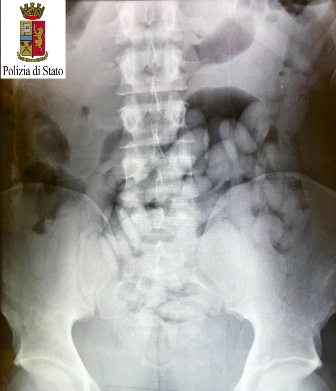

Dopo la prima perquisizione personale che ha avuto esito negativo, gli investigatori hanno ipotizzato che potessero essere due spacciatori e hanno condotto i due sospetti all’Ospedale di Susa per accertamenti.

Le lastre hanno mostrato all’interno della cavità gastrica la presenza di numerosissimi ovuli.

I numeri comunicati dalla Questura sono importanti: durante la permanenza presso il carcere “Lorusso e Cotugno” di via Aglietta, a Torino, il cittadino maliano ha evacuato 109 ovuli di cocaina, per un peso complessivo di 1246 grammi; il cittadino nigeriano ne ha espulsi 72, per un peso complessivo di 790 grammi.